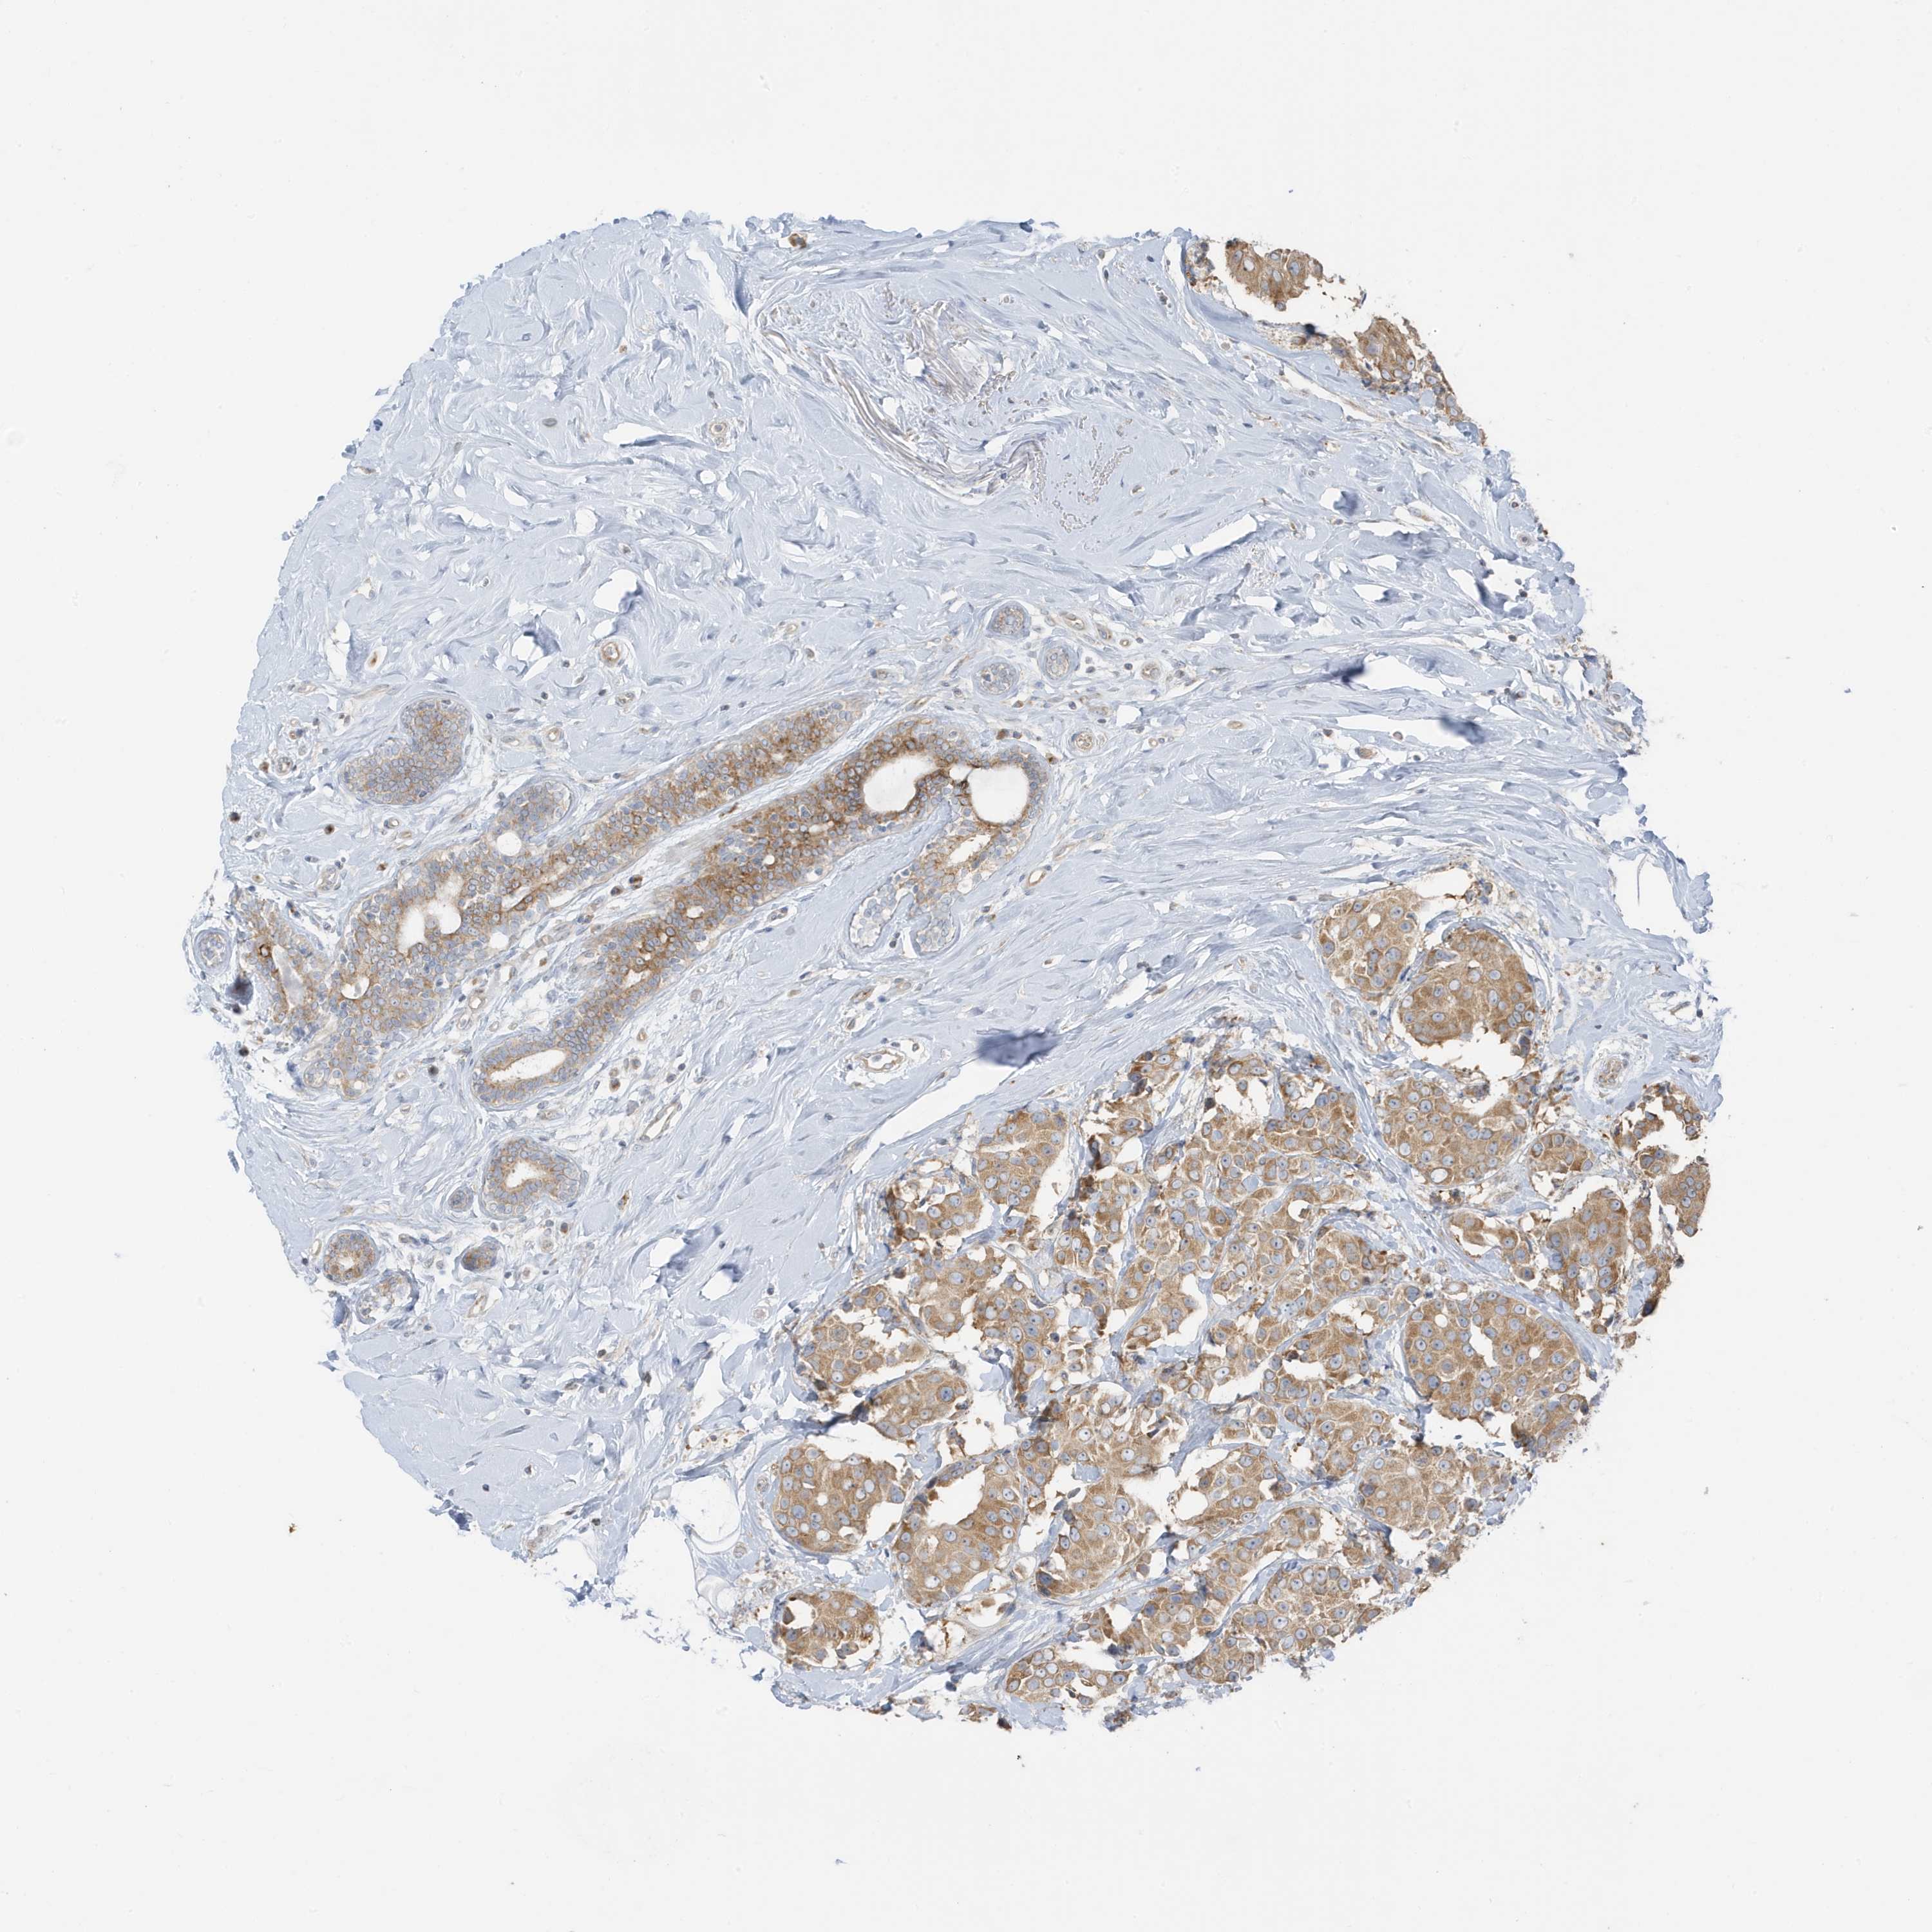

CANCER BREAST CANCER Show tissue menu

BRCA TCGA BRCA VALIDATION PROTEIN EXPRESSION